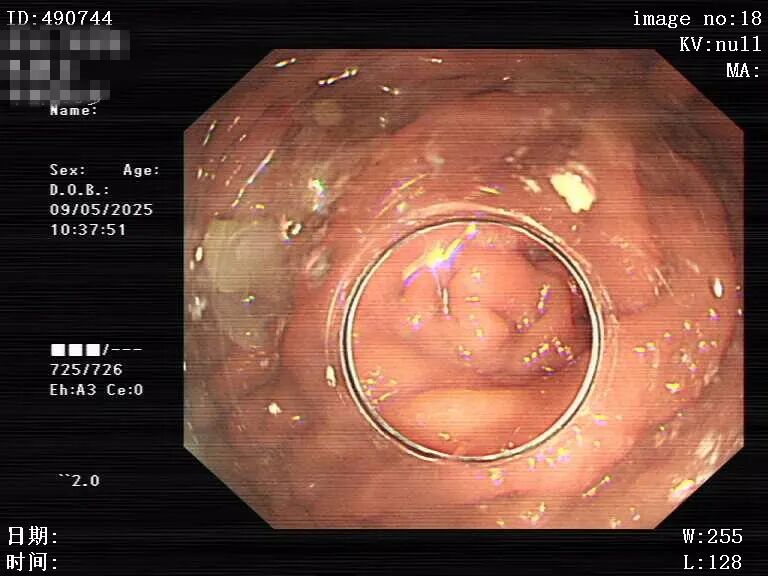

面对患者的抗拒和不配合,消化内科团队始终保持耐心与责任感,他们不断安抚患者情绪,与家属充分沟通。5月2日,当再次胃镜检查发现胃腔内有最大直径约10cm的巨大团块状食物团呈结石状。考虑患者胃石巨大,无法直接取出,且因消化道出血症状来诊,有外科手术指征。“如果我们消化内科不为患者进行内镜处理的话,患者处于90岁高龄,身体条件差,进行外科手术的风险极高,相比较之下,外科手术更不利于患者恢复。”消化内科叶营主任带领团队从患者实际情况出发,当即决定采用分次碎石治疗的方案,尽可能将手术对患者的影响降低。

图片

碎石治疗

在经过与患者及家属的充分沟通后,消化内科团队决定采用内镜下分次碎石及取石术。术中,消化内科团队不仅要克服技术上的难题,还要应对患者的不配合以及胃腔散发的弥漫恶臭。消化内科团队凭借精湛的技术和高度的责任感,历经三次内镜下碎石及一次内镜下取石,最终成功为患者解除了病痛,让患者顺利出院。患者家属在整个治疗过程中深受感动,反复夸赞消化内科团队:“从没见过这么有耐心及责任心的医生。” 这番发自肺腑的表扬,是对消化内科团队最好的肯定。